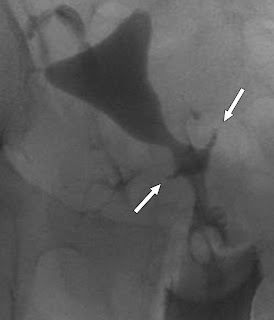

Hysterosalpingogram in 37-year-old woman shows linear cesarean section scar defect at uterine isthmus (arrows).